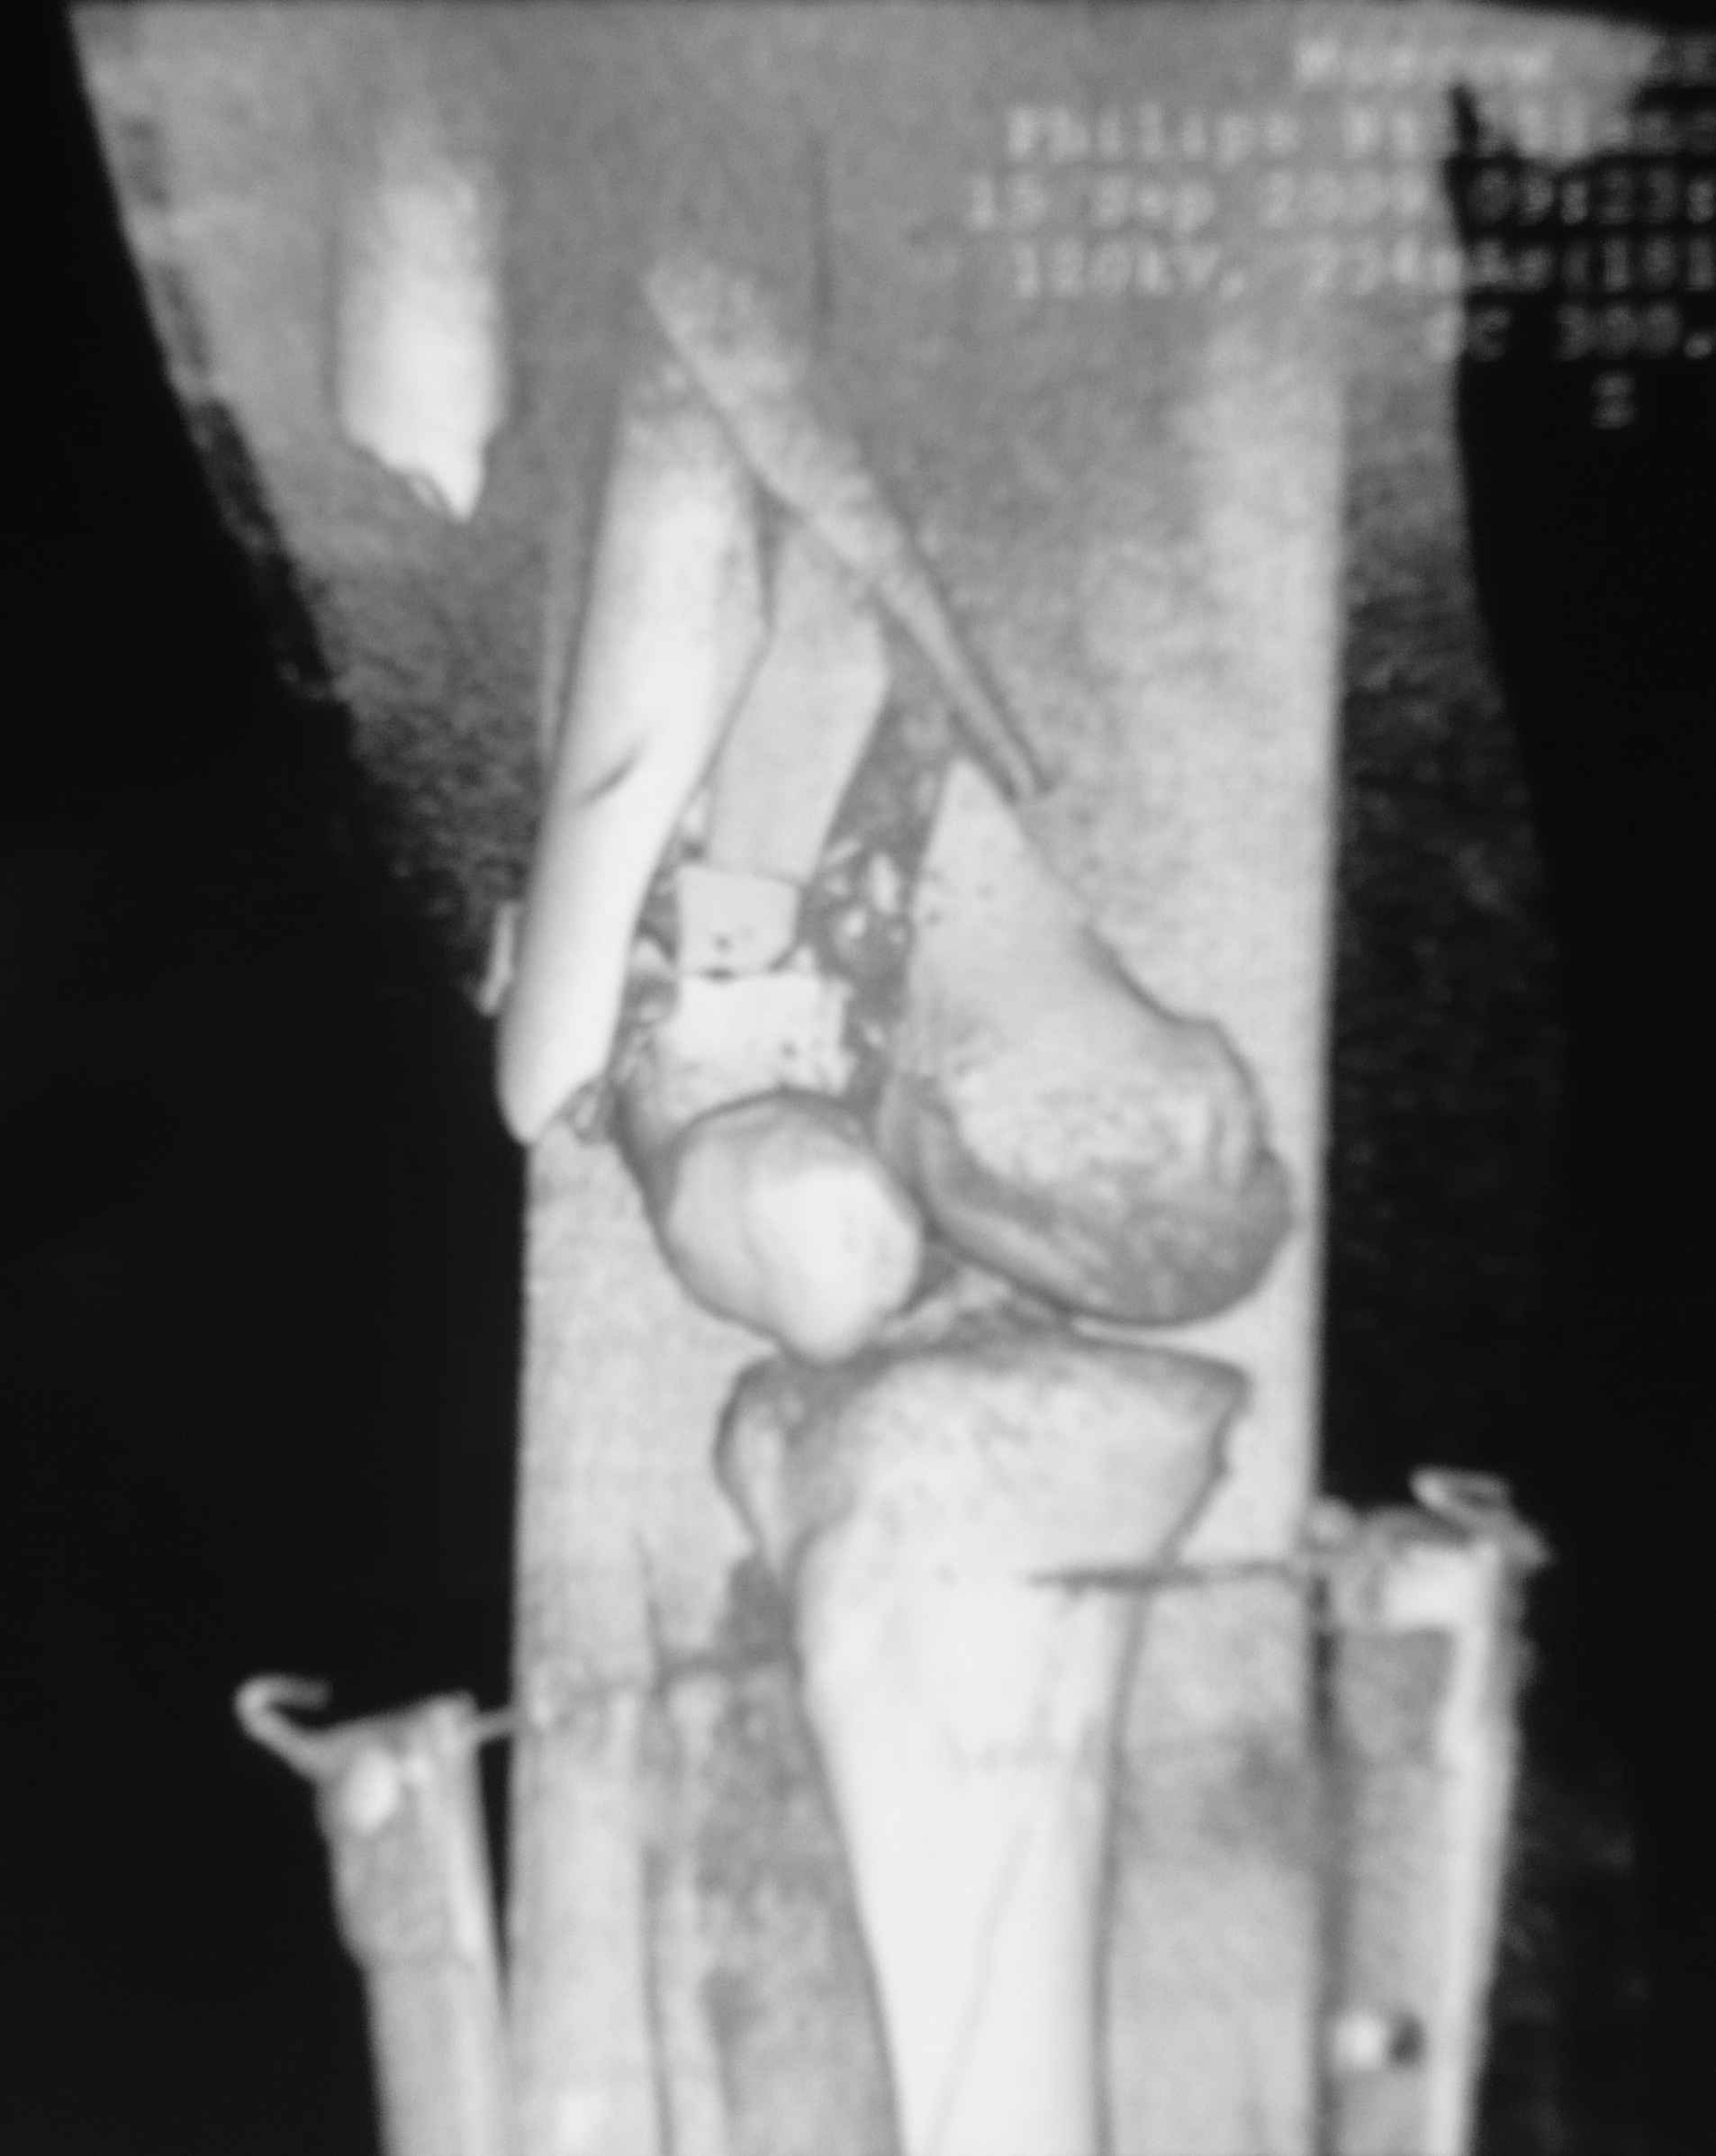

[Ortho] Дистальный перелом бедра

Вообще насчет пластины думали... но если открыться то рассыпится все... LISS можно но тоже тяжело представить...